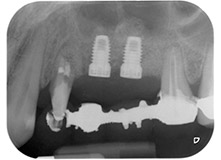

Fig. 1: 58-year-old patient. Preoperative radiograph showing an apical periodontal lesion at tooth 24 and horizontal loss of alveolar bone in the second quadrant.

A 58-year-old female patient complained of pain and increased mobility of her bridge abutment tooth 24. Periodontal inflammation was present with pocket depths of 7 mm mesiobuccally and more than 12 mm distally, as well as third-degree furcation involvement. Moreover, the radiograph revealed an extensive periodontal lesion around the apical region of the (alio loco) endodontically pretreated tooth 24 (Fig. 1).

One year earlier, teeth 25 and 26 had been extracted due to trauma and for endo-perio reasons, prior to the placement of the bridge. A combined endo-perio lesion was diagnosed for tooth 24, of unclear aetiology. The patient wanted to keep her bridge abutment teeth 24 and 27 and would not accept a final, or even temporary, removable prosthesis. Therefore, it was agreed to make all efforts to retain both teeth, in spite of their poor prognosis as based on radiological and clinical findings.